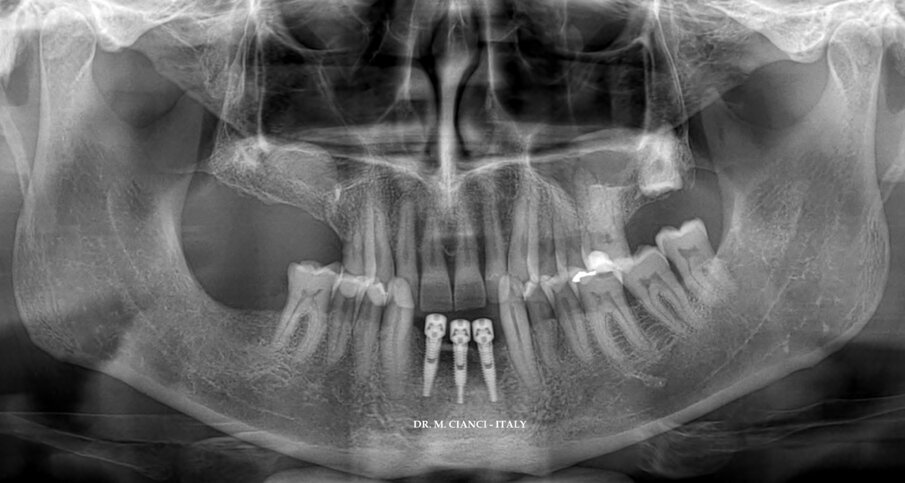

Sei mesi dopo la GBR il controllo tomografico confermava il successo della rigenerazione (Fig. 4) per cui sono stati inseriti 3 impianti narrow Piattaforma 3.0 INTERNA BTI diametro 3.0 mm equamente distanziati tra i due canini: la connessione interna esalobulata (Fig. 5) permette il carico immediato anche con impianti di diametro così ridotto evitando i punti di affaticamento con una buona distribuzione dei carichi assiali, laterali e di torsione4; la superficie implantare UnicCa, ottenuta attraverso una modifica con ioni di calcio e tipica di tutti gli impianti BTI, è una superficie elettropositiva, pulita e super-idrofilica, stimola l’attività osteogenica e promuove la stabilità ossea peri-implantare minimizzando l’aderenza batterica e favorendo la conservazione dei tessuti marginali5-7 (Fig. 6).

Fig. 2 - Immagine 3D della mandibola a un mese dalle avulsioni dentarie.